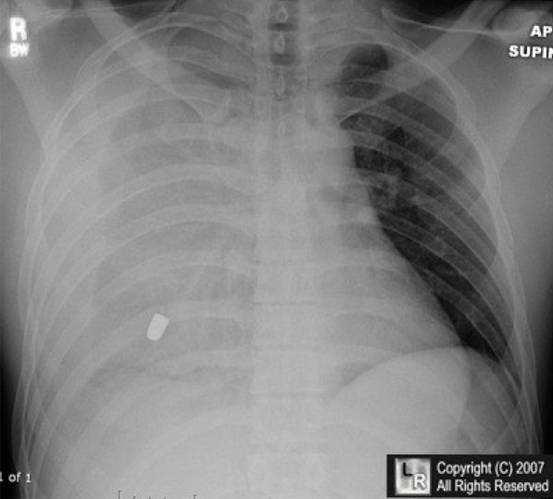

6.男性,24岁,车祸来诊,诉右侧胸痛,胸片如下,考虑诊断:

A. 左侧气胸

B. 右侧血气胸

C. 急性左心衰

D. 右侧肺不张

E. 肺炎